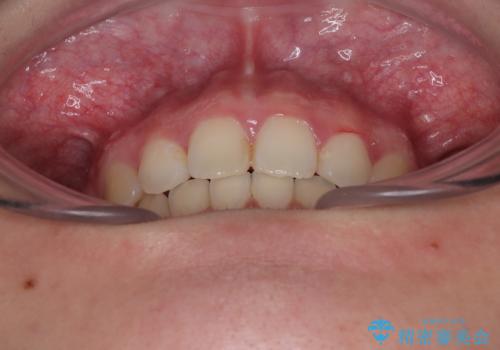

- 下唇の上に乗っかってしまうくらい前歯が飛び出していることを気にして来院された患者様です。

唇を閉じようとするとオトガイ部に力が入ってしまい、うまく閉じることができない状態であったため、上下左右の第一小臼歯4本を抜歯して、ワイヤー装置にて矯正治療を行うこととしました。

飛び出した前歯はしっかりと引っ込み、横顔の印象が大きく変化しました。